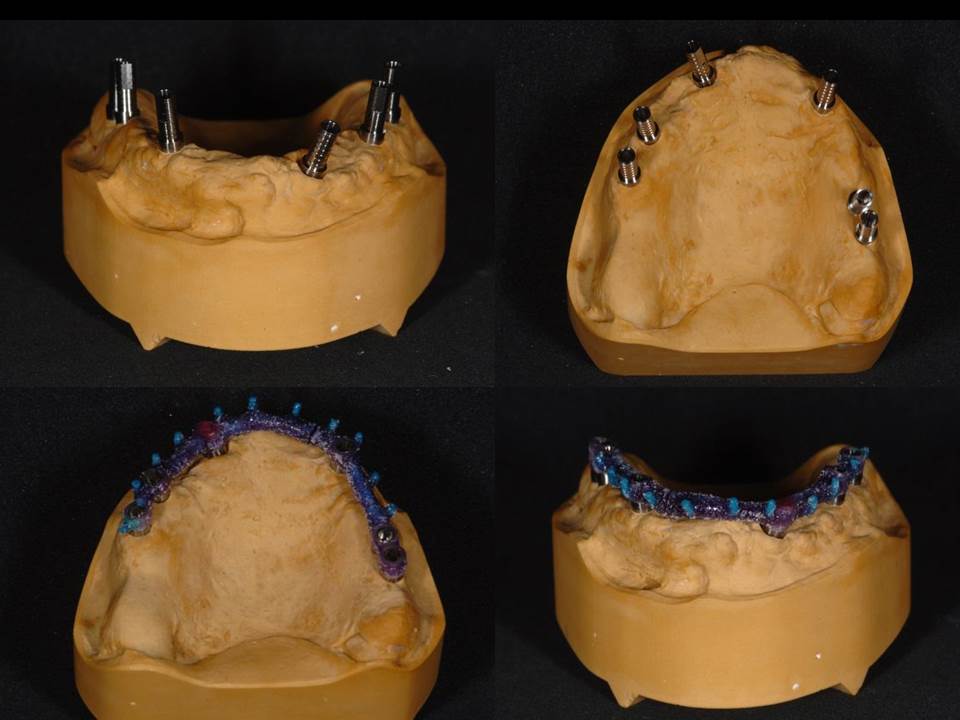

Prótesis fija OT BRIDGE

E - BOOK y CASOS CLÍNICOS

CASOS CLÍNICOS